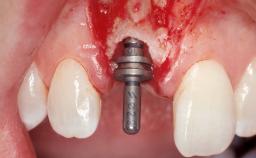

Immediate Flapless Placement of an Implant in a Maxillary Left Central Incisor Site

A 29-year-old female patient presented for treatment to replace the upper left central incisor tooth with an implant- supported restoration. The tooth had been intermittently symptomatic for the previous 12 months. The tooth had originally suffered trauma about 15 years previously. Several endodontic treatments had been performed, including an apicectomy procedure to retain the tooth. The patient was healthy and a non-smoker. She had reasonable expectations in regard to esthetic outcomes and the risk of marginal tissue recession following treatment. At medium smile, the gingival margins of the upper teeth were visible, with a display of 3 to 4 mm of the gingival margins. Gingival recession of tooth 21 and a discrepancy in the gingival levels between teeth 11 and 21 was observable during normal speech and smile.